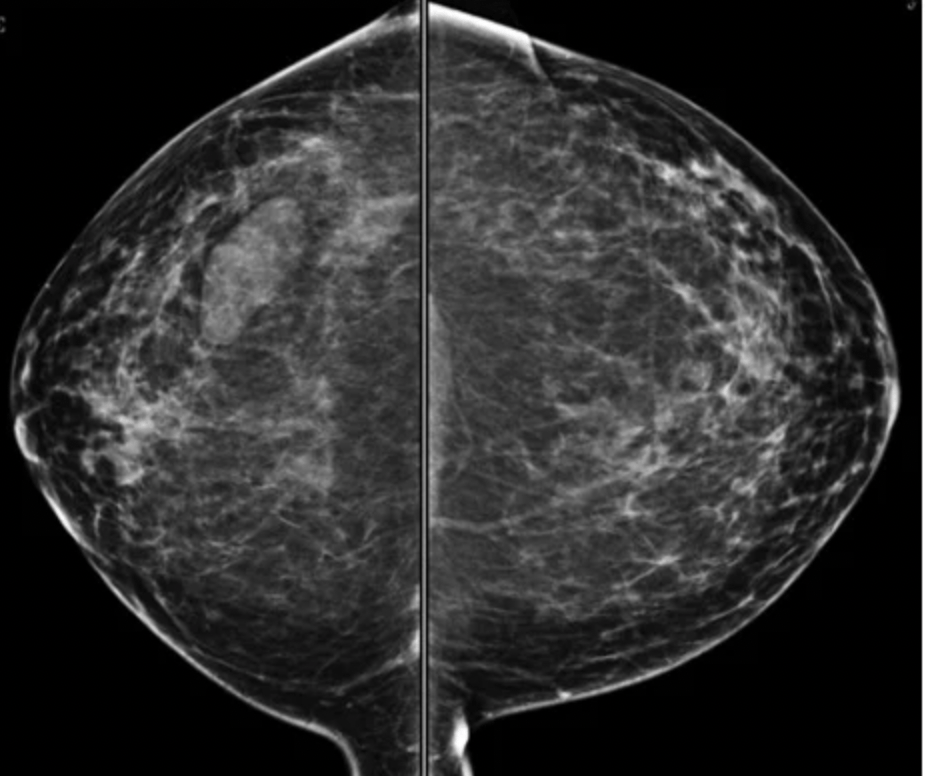

Imaging: bilateral MLO and CC views of the breasts. There is an ovoid mass in the right lower, outer quadrant.

- On mammography:

- The most common appearance described is:

- A well-defined, uncalcified mass, with regular borders

- Spiculated borders, suspicious borders, and architectural distortion can also be seen:

- But are uncommon